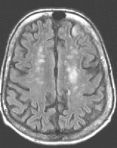

Fig. 1 Fig. 2 Fig. 3 Fig. 4

MRI Findings: In the supratentorial regions, some atrophy and chronic small vessel deep white matter ischemic changes were observed (Fig. 1) but no acute lesion or infarct was observed on MR diffusion. In the posterior fossa, however, a subtle small 1 cm hyperintensity can be seen in the left side of medulla on T2 weighted (Fig. 2) and FLAIR images (Fig. 3). This can be seen with an infarct, but its age would remain indeterminate. The MR diffusion image (Fig. 4) shows hyperintensity in the same region consistent with an acute infarct (arrows) as opposed to chronic ischemic changes.